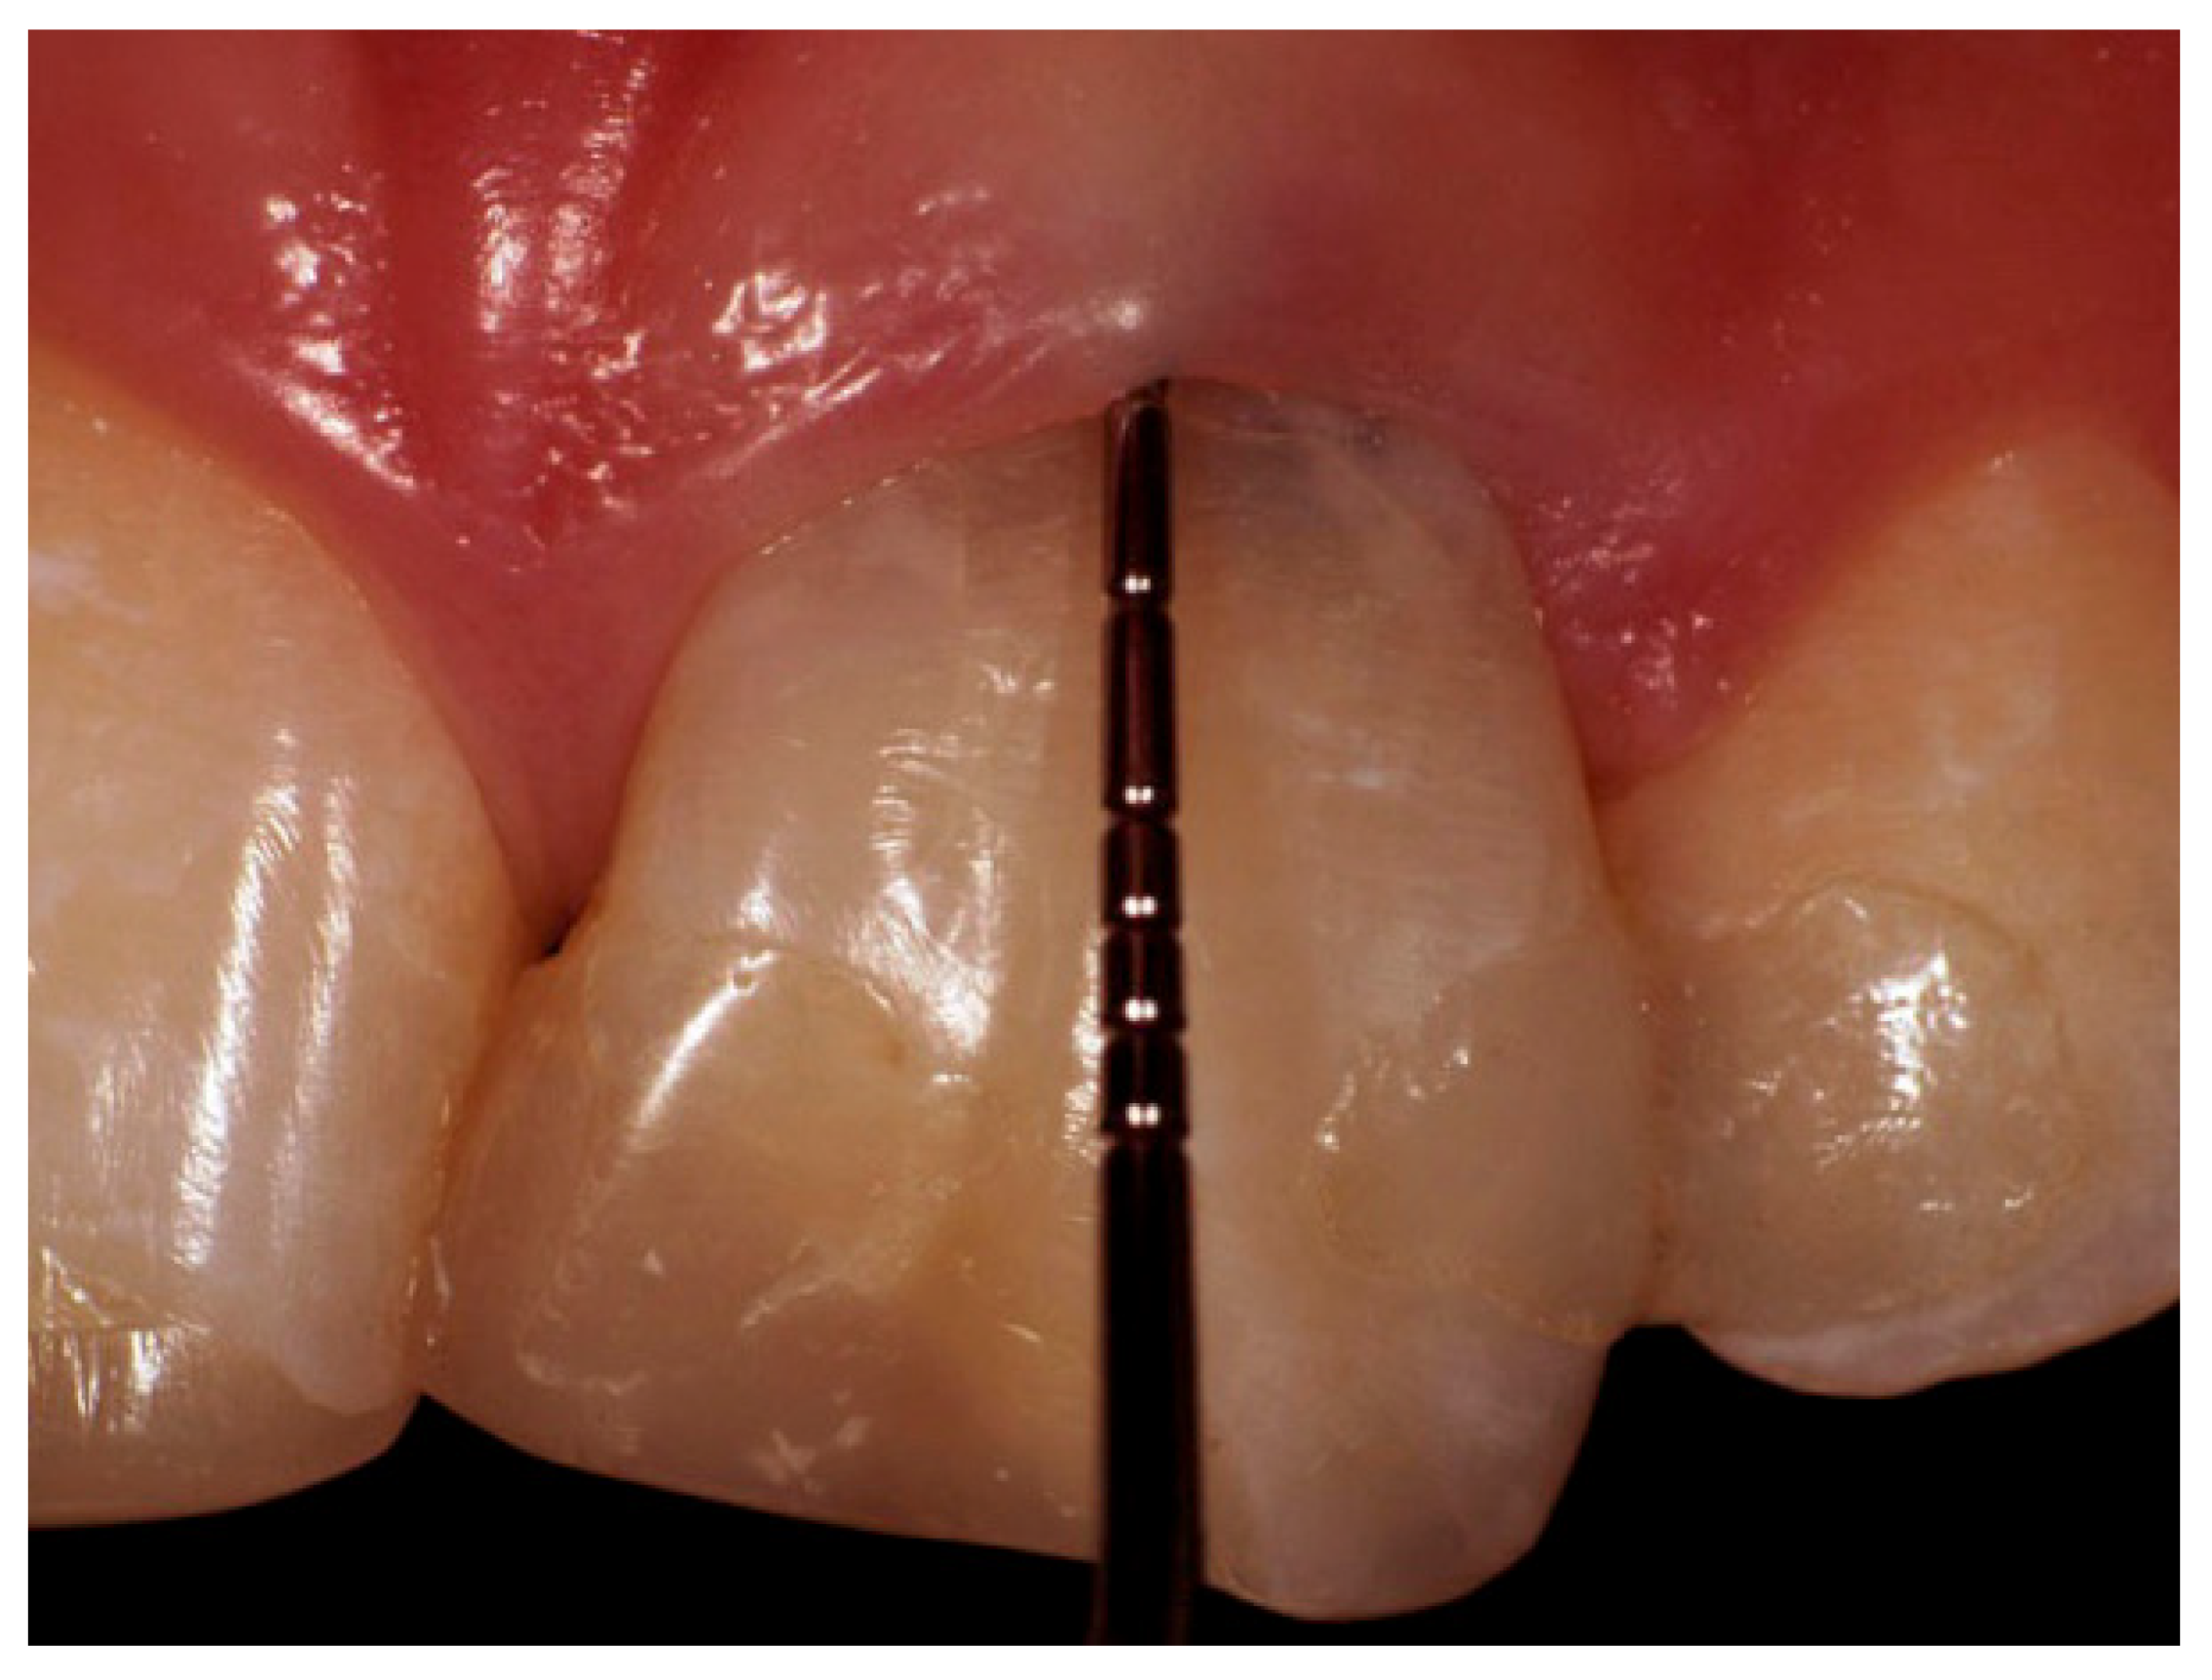

2. Case Presentation